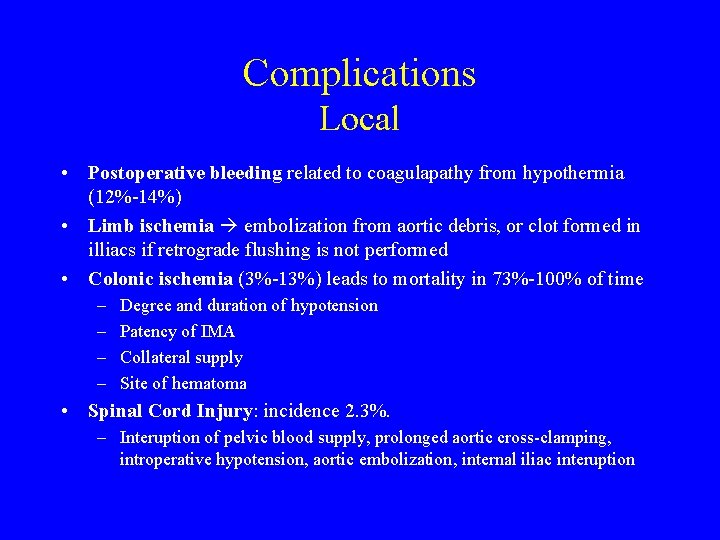

Complications Local • Postoperative bleeding related to coagulapathy from hypothermia (12%-14%) • Limb ischemia embolization from aortic debris, or clot formed in illiacs if retrograde flushing is not performed • Colonic ischemia (3%-13%) leads to mortality in 73%-100% of time – – Degree and duration of hypotension Patency of IMA Collateral supply Site of hematoma • Spinal Cord Injury: incidence 2. 3%. – Interuption of pelvic blood supply, prolonged aortic cross-clamping, introperative hypotension, aortic embolization, internal iliac interuption